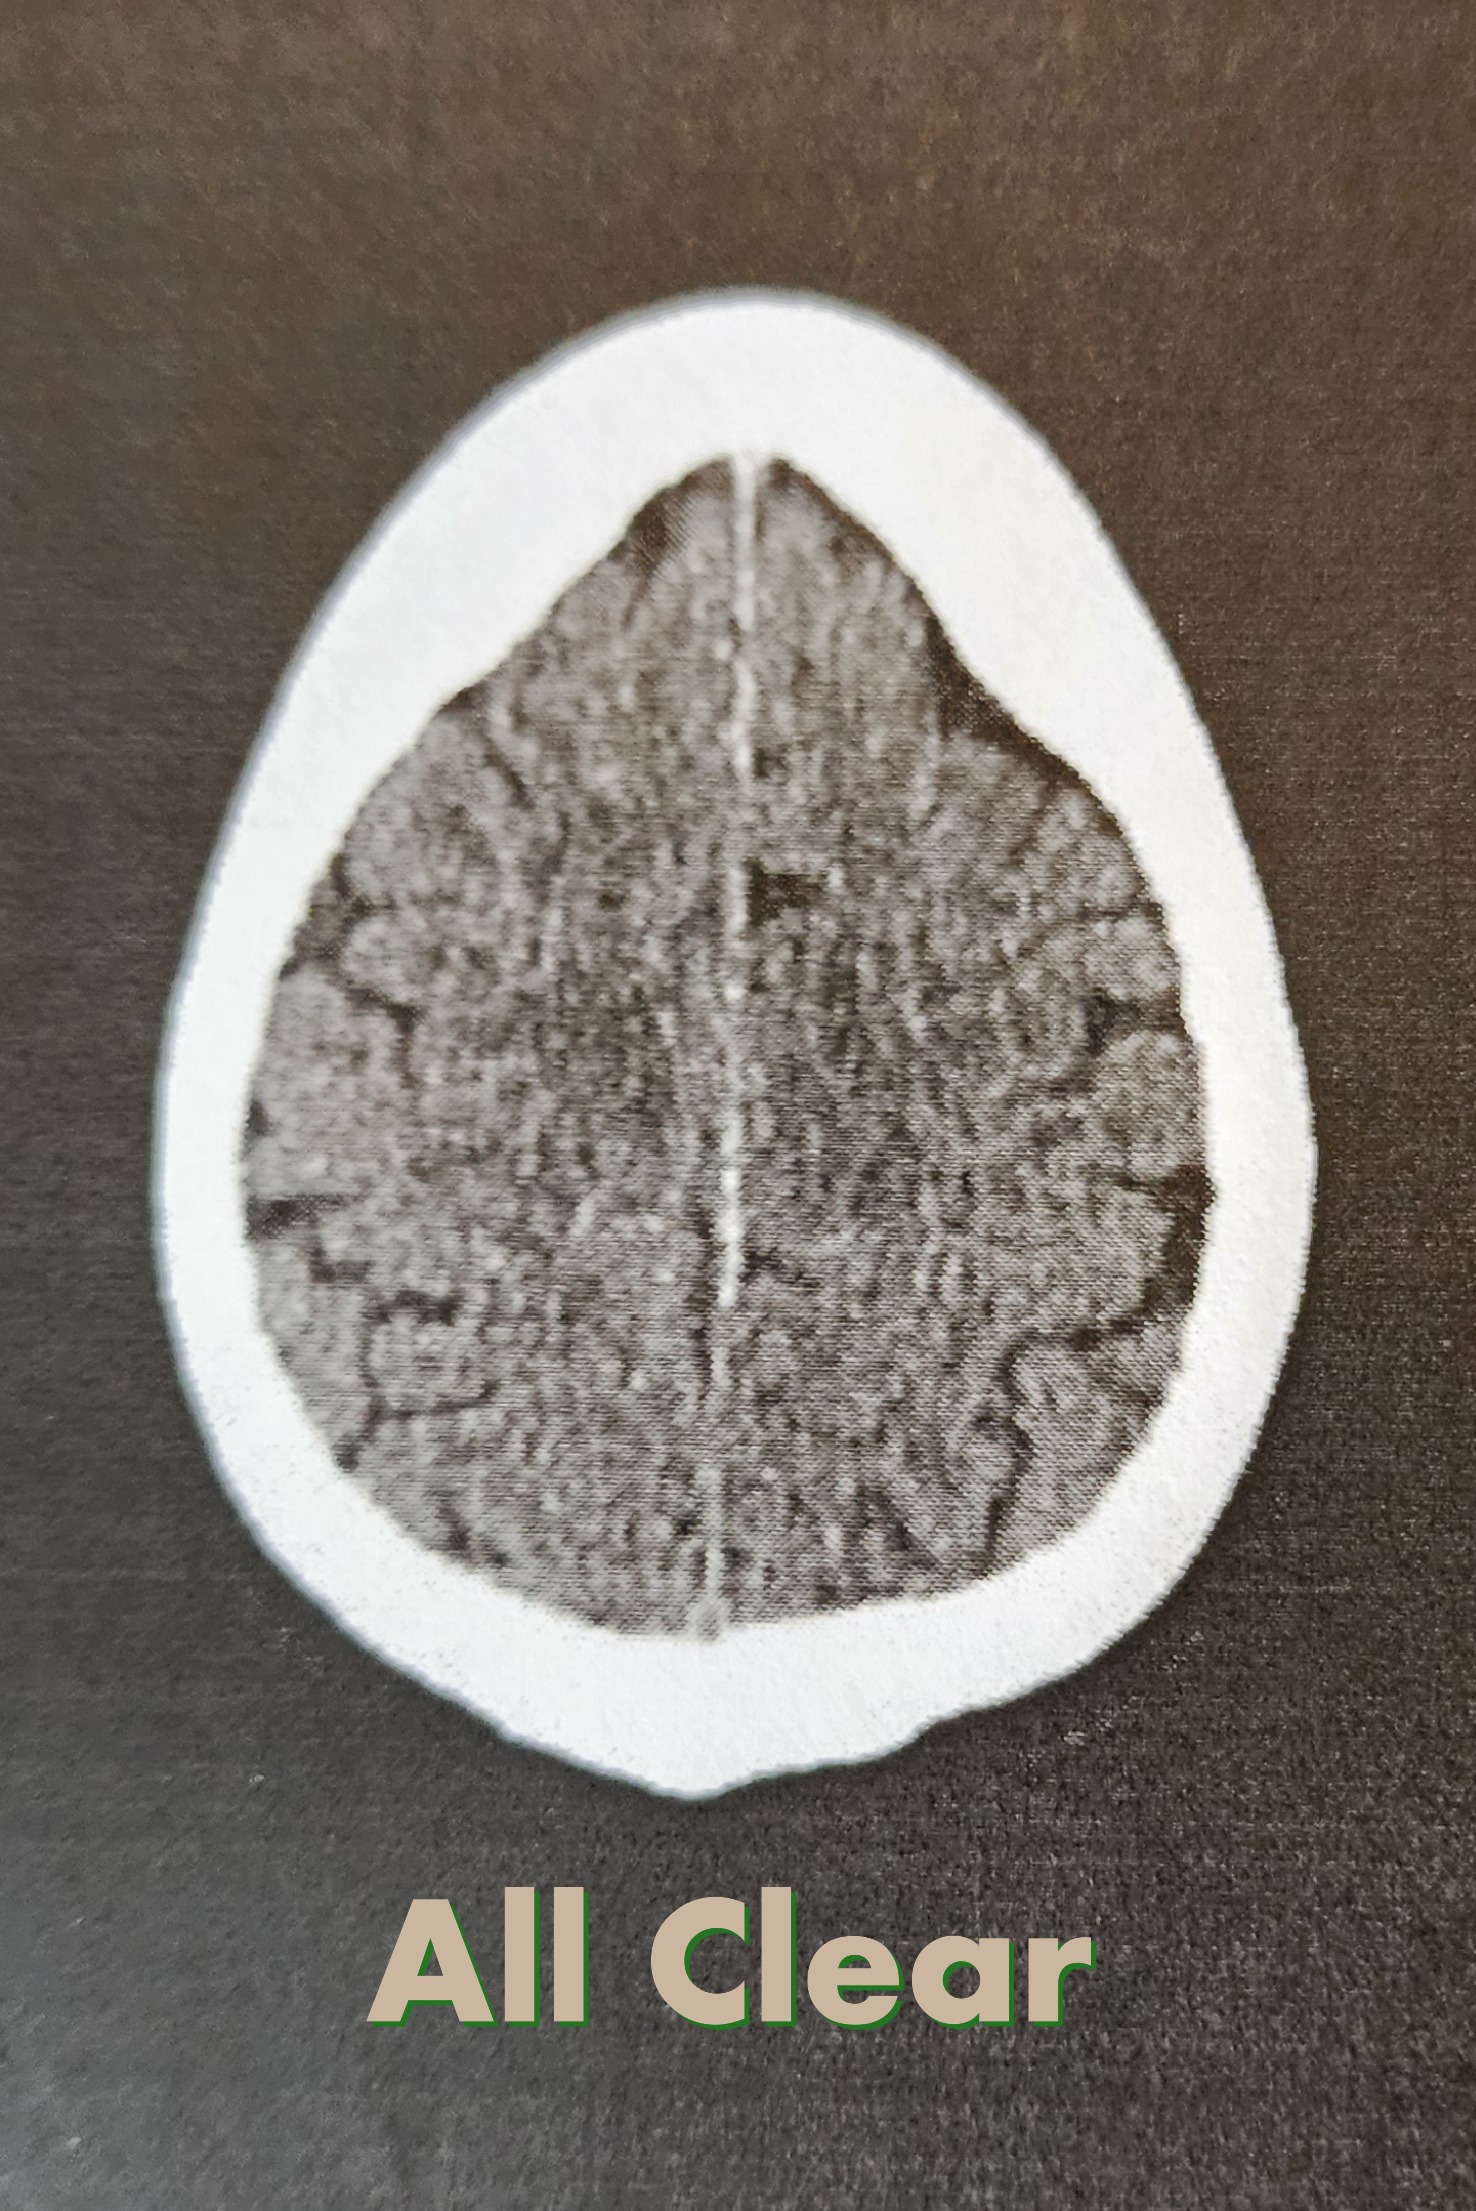

Cleared and Back to Normal Ready to Ride Motorcycles

The good news? I’m now fully cleared to return to normal activities. That means riding, writing, riding, creating, and sharing again. I’m grateful for the care I received and for the reminder that even when you “just want to ride,” your health always comes first.